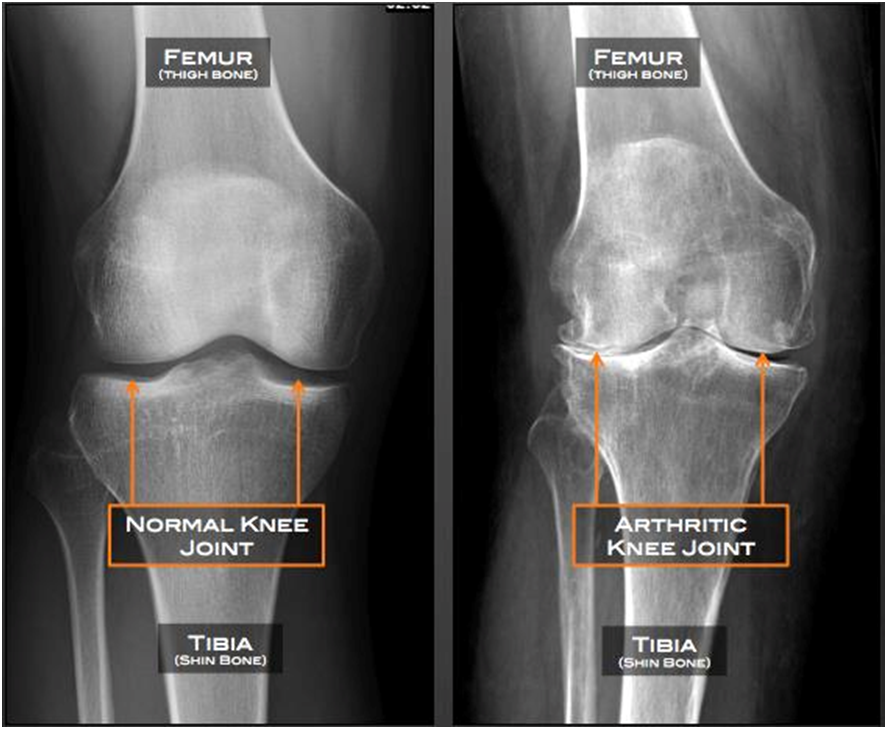

Knee osteoarthritis (OA) is a common joint problem that occurs when the cartilage in the knee wears down over time. This leads to pain, stiffness, and difficulty in movement. It mostly affects people above the age of 50 but can also develop earlier due to injuries or other risk factors.